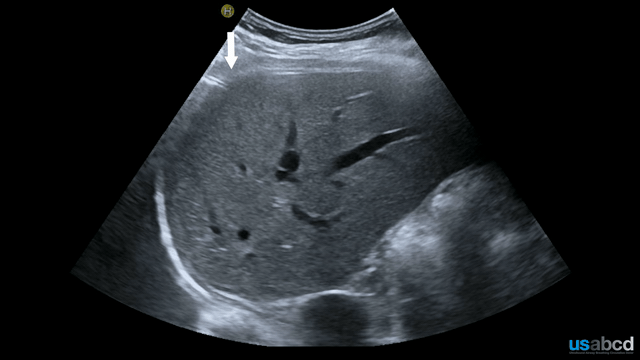

This clip shows a large pleural effusion in the left thoracic cavity. The spleen is seen below the diaphragm, with fluid visible above it. The absence of the curtain sign and the presence of the spine sign confirm the effusion. A small rim of compressed lung tissue is visible above the diaphragm within the fluid.